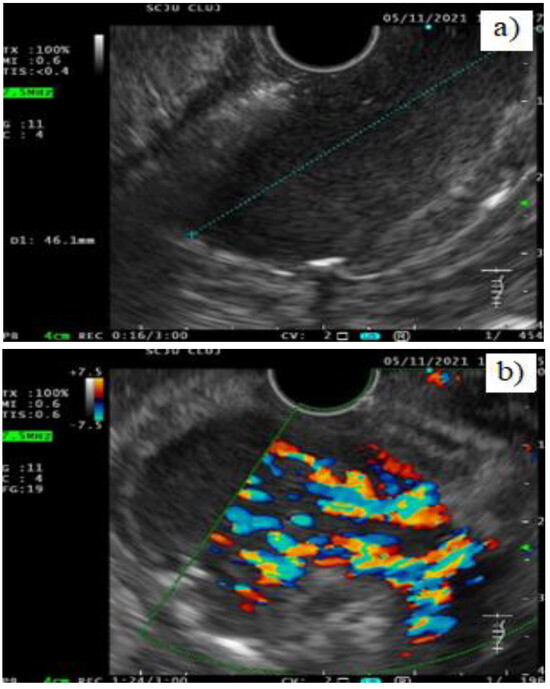

Case presentation